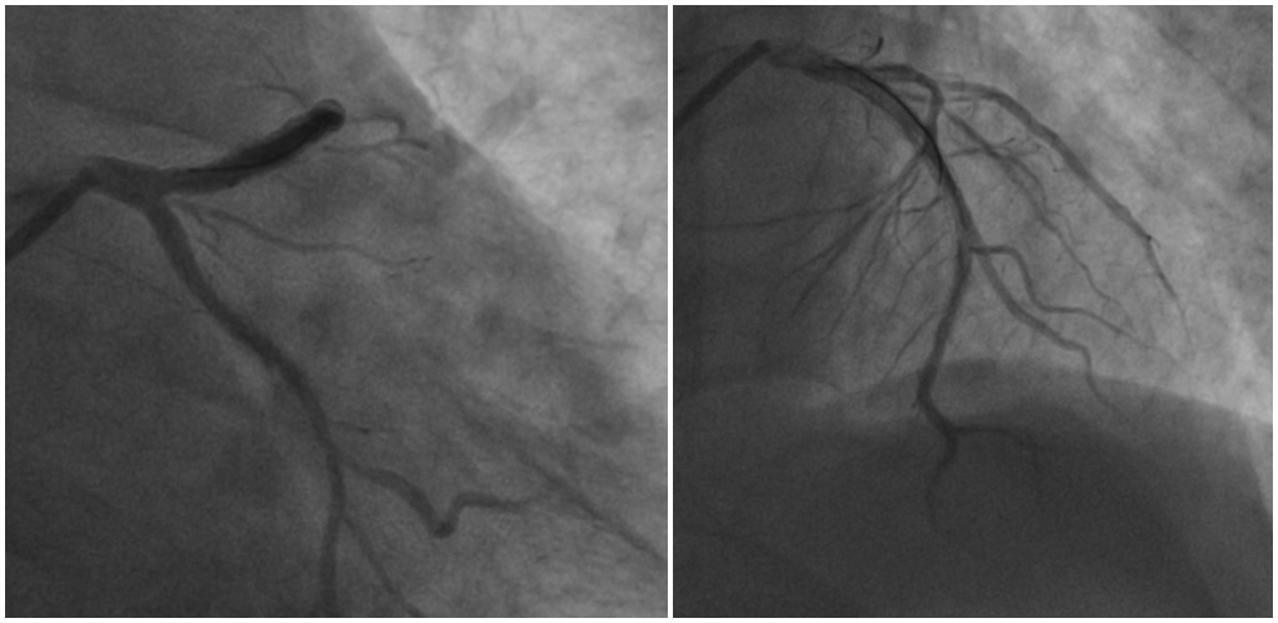

冠脉造影完成,前降支(LAD)近段90%弥漫狭窄,前向血流TIMI0级;回旋支(LCX)硬化,前向血流TIMI1-2级。右冠脉(RCA)近段75%狭窄、中段闭塞,前向血流TIMI0级。(图2)。

图2. 左冠造影结果